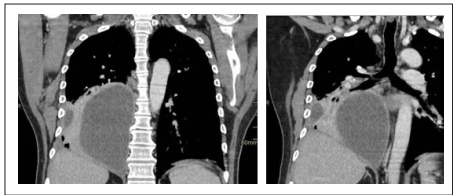

Hombre de 48 años con antecedentes de hipertensión arterial, hiperuricemia y prediabetes en manejo ambulatorio con losartan y alopurinol. Ingresa al servicio de urgencias por un cuadro clínico de un mes de evolución consistente en disminución de la clase funcional, perdida de 6 kilogramos involuntariamente en una semana, dolor de características pleuríticas en hemitorax derecho y picos febriles cuantificados en 40 °C; Se encuentra paciente con estabilidad hemodinámica, sin signos de dificultad respiratoria, taquicárdia, desaturado, afebril con estertores finos y disminución de murmullo vesicular en ambas bases pulmonares. Dentro de los paraclínicos de ingreso resalta una PCR (Proteína C reactiva) elevada, un hemograma con leucocitosis y neutrofilia, gases arteriales con trastornos de la oxigenación con lactato normal y función renal conservada, tabla 1. Se solicita una radiografía de tórax con una opacidad que compromete la totalidad del lóbulo inferior derecho con abombamiento de la cisura mayor, obliteración del ángulo costo frénico lateral derecho por engrosamiento y/o derrame pleural (Ver Imagen 1). Se solicita tomografía de torax con contraste, la cual muestra una obliteración del bronquio para el segmento medial basal del lóbulo inferior derecho, nódulos solidos de distribución aleatoria en el segmento medial lateral del lóbulo medio de hasta 5 mm de diámetro, atelectasia casi completa del lóbulo inferior y una colección pleural derecha de 113 x 132 mm con realce de la pleura al medio de contraste (Ver Imagen 2). Ante hallazgos imagenológicos y persistencia de picos febriles, taquicardico, con requerimiento de oxígeno se inicia cubrimiento antibiótico con Piperacilina Tazobactam (dosis 4,5 gramos cada 6 horas), sin considerar en el momento macrólido debido a cuadro de neumonía no grave, reporte de alta resistencia de macrólido del Streptococcus pneumoniae en Colombia y adicionalmente con plan de estudio de líquido pleural. Se amplían estudios con VIH negativos, perfil hepático, electrolitos normales, hemoglobina glicosilada en rango de prediabetes y ácido úrico normal (Ver tabla 1). Debido a temporalidad de síntomas, paraclínicos con leucocitosis con neutrofilia, PCR elevada y hallazgos imagenológicos se considera causa de etiología bacteriana por lo cual no se realizó panel viral respiratorio. En manejo multidisciplinario con el grupo de cirugía de tórax se realiza drenaje de colección con hallazgos de líquido turbio y de características purulentas por lo cual se decide la colocación de dren; En el análisis inicial de líquido pleural cumple criterios de exudado paraneumónico complicado, con estudios de tuberculosis negativo, hallazgos de bacterias con morfología de cocos Gram positivos con tipificación de Streptococcus pseudoporcinus, con sensibilidad a penicilina. Debido Según lineamiento de guías sobre empiema, en un paciente sin exposición antibioticoterapia previa, no aislamiento o acceso a servicios de salud para pensar en gérmenes resistentes se decide desescalonar manejo antibiótico a ampicilina - sulbactam (3 gramos cada 6 horas). Quien debido a complicación de derrame paraneumonico complicado por características purulentas de drenaje con un alto drenaje se decide completar 30 días de manejo antibiótico de manera ambulatoria, que debido a evolución clínica satisfactoria se indicó manejo a vía oral con amoxicilina a 1 gramo cada 6 horas después de 10 días de manejo antibiótico intravenoso.